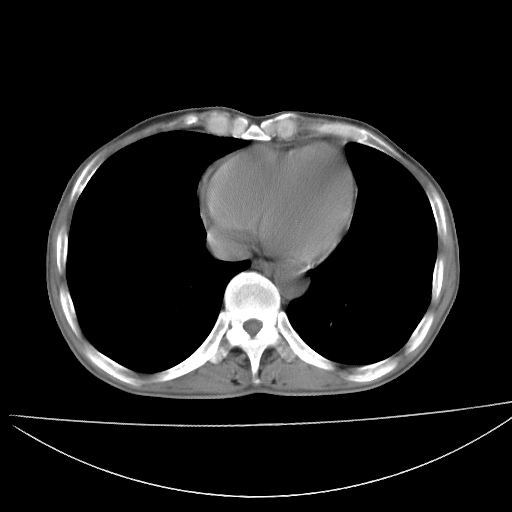

以下是引用杀毒软件在2009-4-28 17:58:00的发言:[br]考虑----左肺慢性肺脓肿形成继发上叶含气不良---抗炎后复查---待排肿瘤所致[br][br][本贴已被 杀毒软件 于 2009-4-28 18:01:26 修改过]